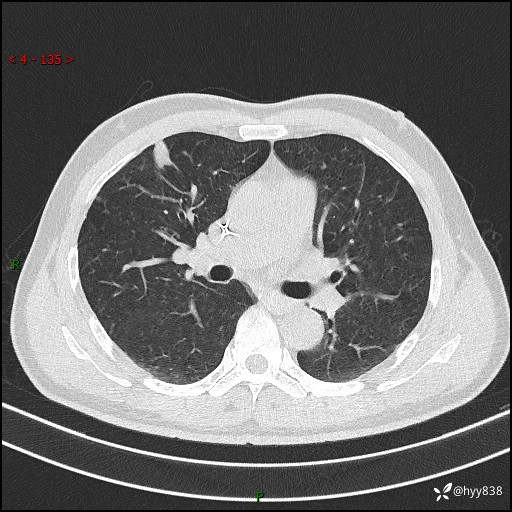

现病史:者10余天前因胸闷就诊于我院心血管内科,行胸部CT提示右肺上叶结节(24mm×16mm),考虑肿瘤性病变可能。无畏寒、发热、盗汗,无咳嗽咳痰,无咯血,无胸痛,无呼吸困难等不适,未予特殊处理。今为求进一步诊治,前来我院就诊,门诊以“肺结节待查”收住入院。 患者自起病来精神、食欲、睡眠尚可,体力下降,体重无明显变化。

胸部CT平扫+增强